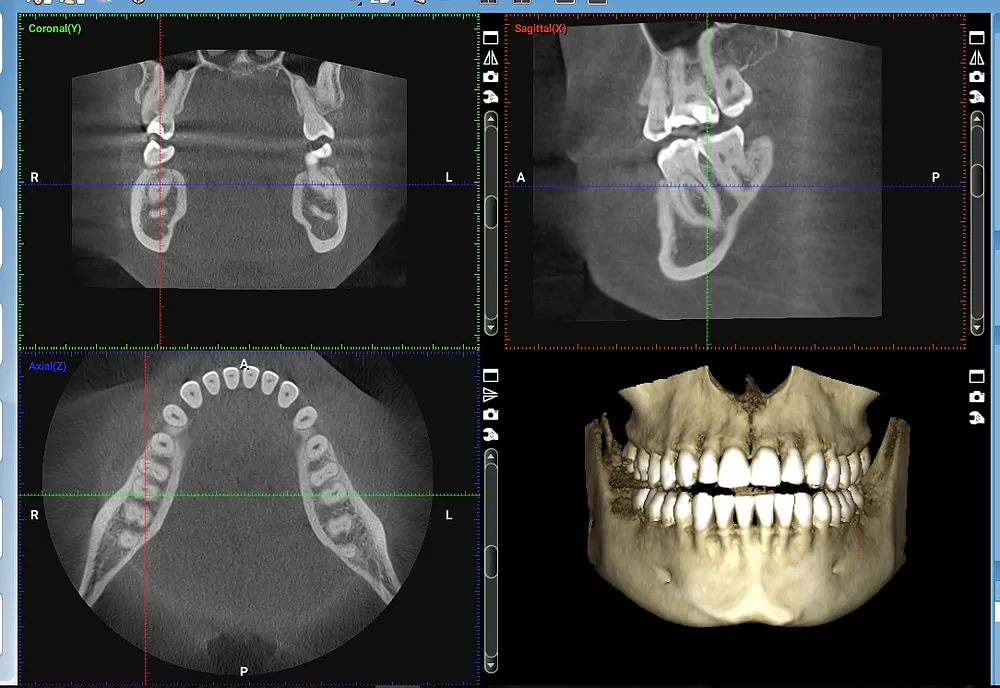

Revolutionizing Dental Implant Planning with CBCT Imaging

Dental implants have come a long way since their inception in the 1960s. From traditional x-rays to advanced technology, the...